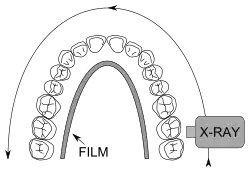

Im November 1895 entdeckte Wilhelm Conrad Röntgen die später nach ihm benannten Röntgenstrahlen, die die Untersuchung des Kiefers vereinfachten. Als Mittel zur örtlichen Betäubung von Zahnschmerzen wurde im Jahre 1905 das Lokalanästhetikum Procain von den deutschen Chemikern Alfred Einhorn und Emil Uhlfelder entwickelt, die dem Wirkstoff den Namen Novocain (lateinische Wortschöpfung für „Neues Cocain“) zuordneten. Damit waren die Grundlagen für eine moderne Diagnostik und Therapie gelegt. Die Zahnheilkunde erlebte daraufhin einen rasanten Fortschritt: von der Entwicklung zahlreicher oralchirurgischer Verfahren bis zur Anfertigung von Zahnersatz mittels CAD/CAM-Verfahren. Parallel zum Fortschritt der wissenschaftlichen Zahnheilkunde entwickelte sich das Berufsbild, was in der Geschichte des Zahnarztberufs dargestellt wird. Daneben entwickelte sich die Tierzahnheilkunde, die sich entsprechend modifizierter Verfahren der allgemeinen Zahnheilkunde bedient.